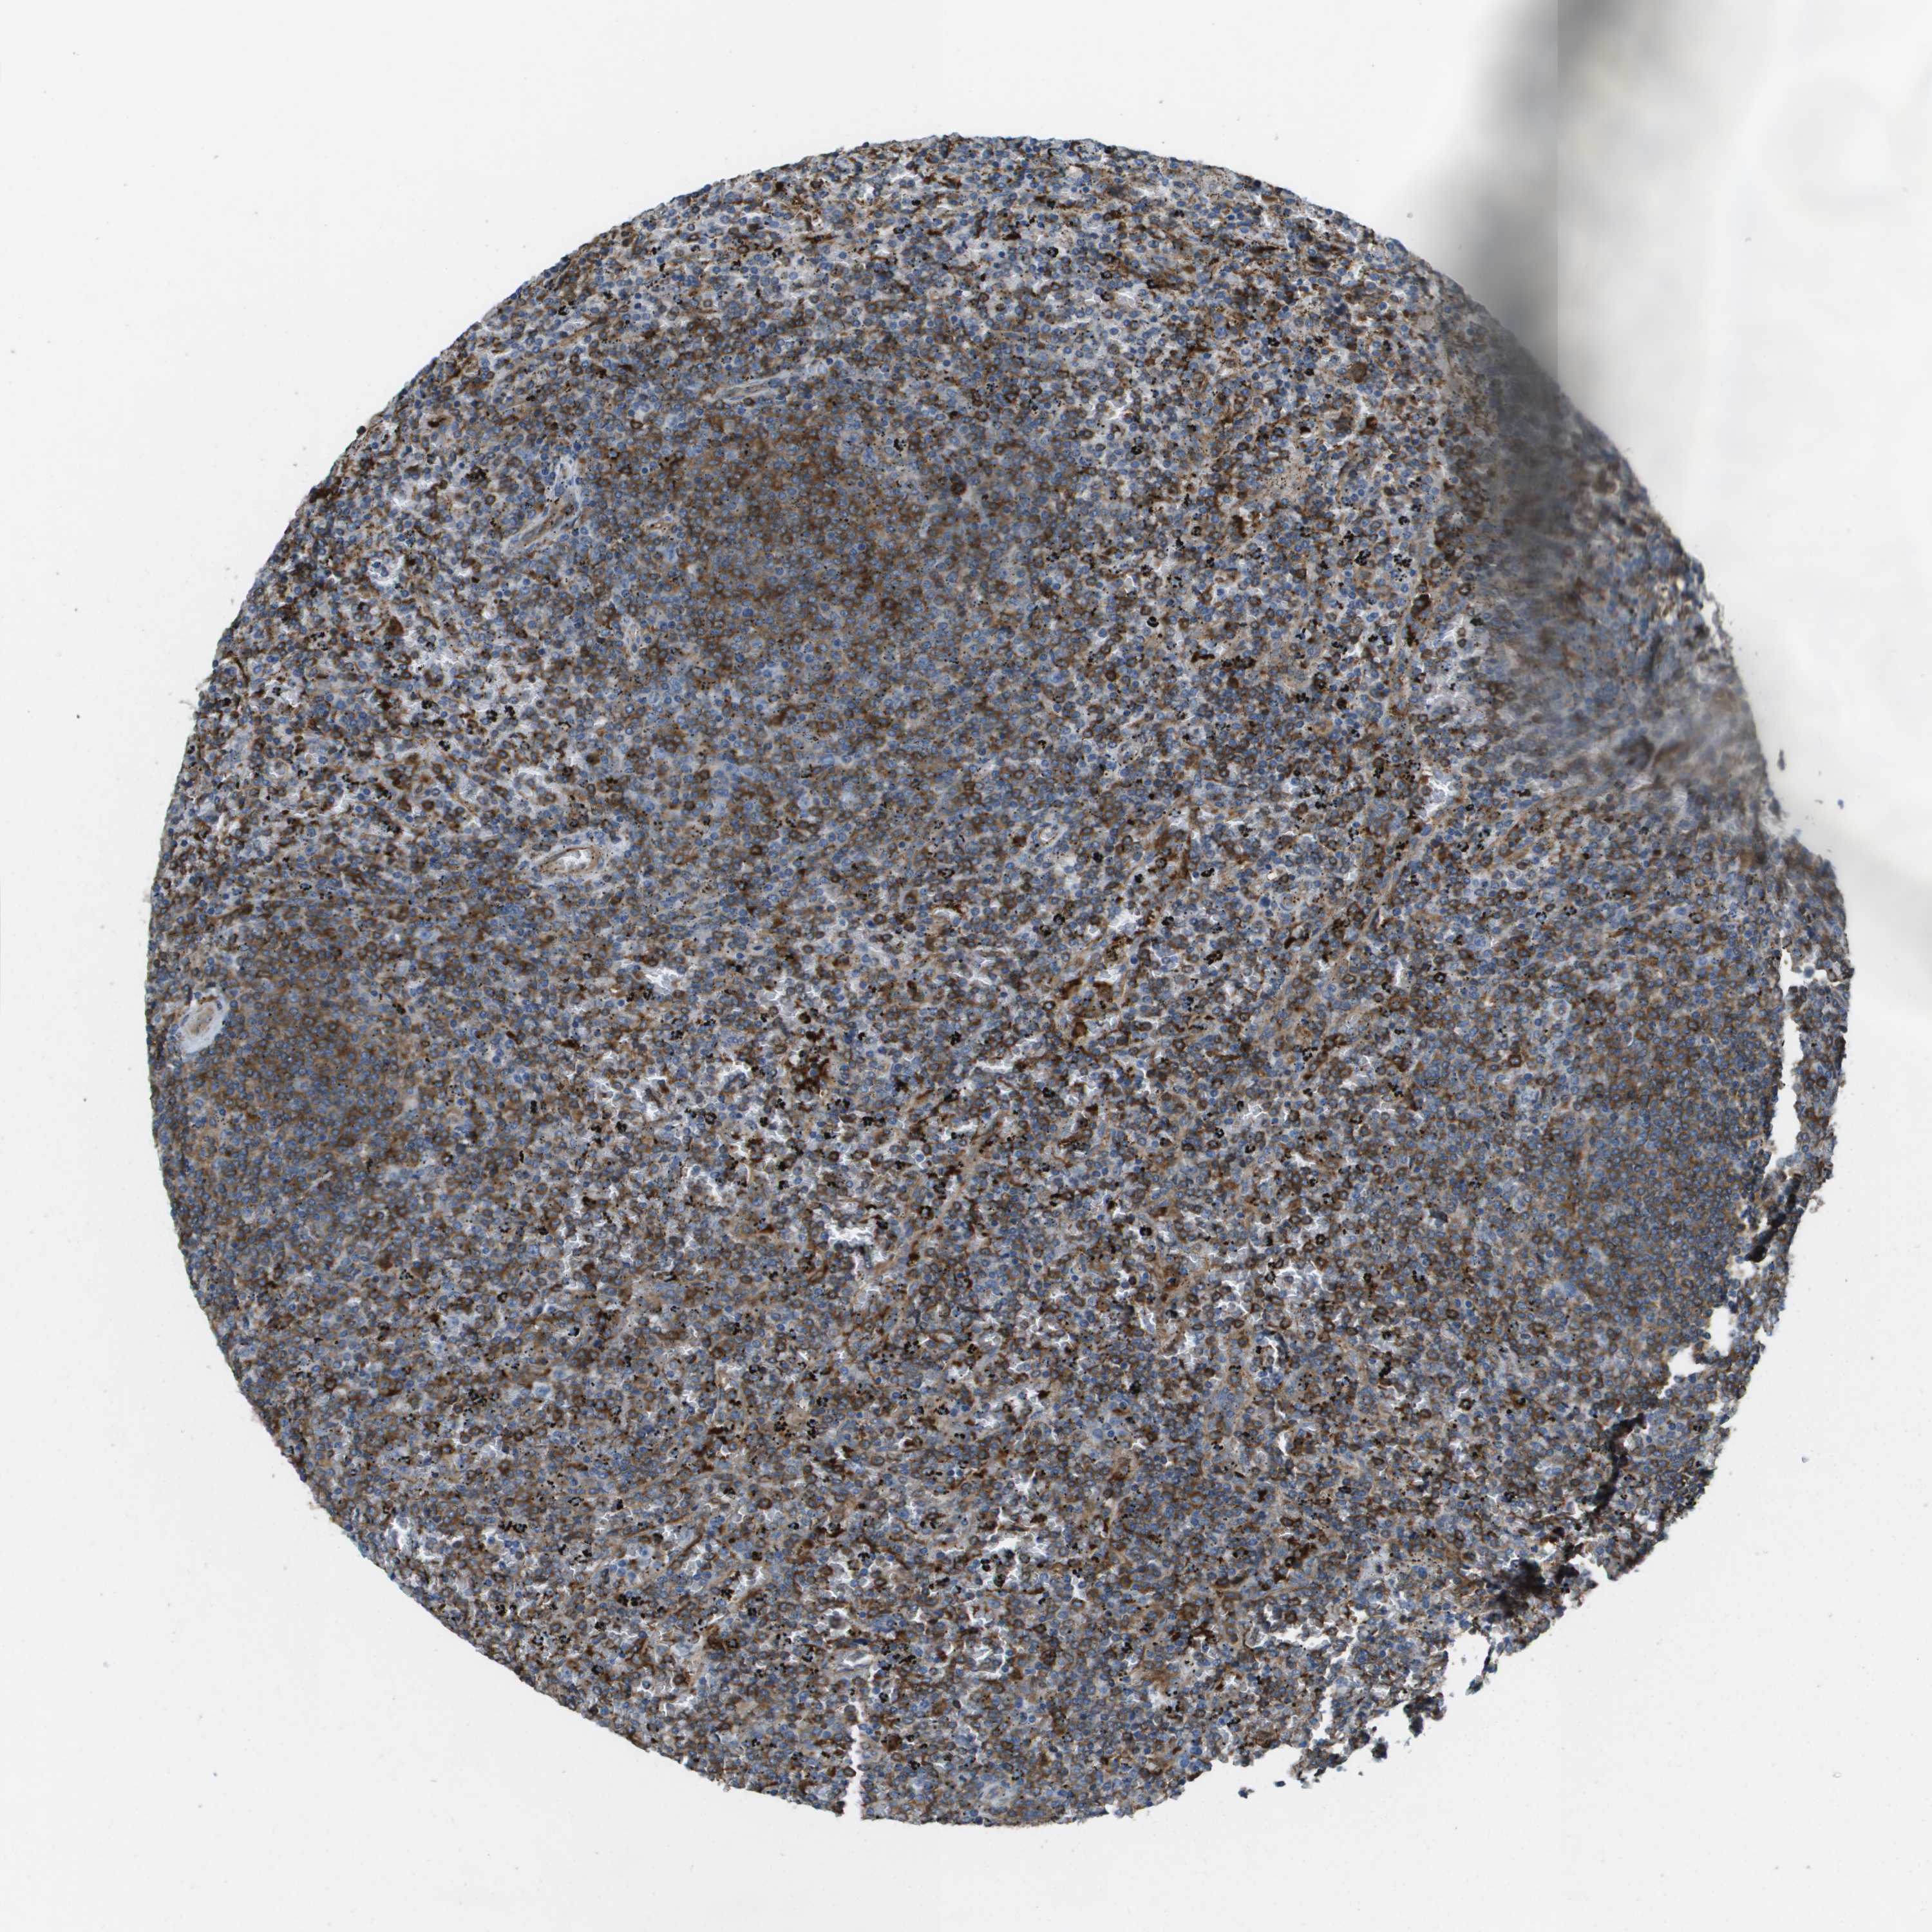

CANCER LYMPHOMA Show tissue menu

LYMPHOMA - Protein expressioni

A mouse-over function shows sample information and annotation data. Click on an image to view it in a full screen mode. Samples can be filtered based on level of antibody staining by selecting one or several of the following categories: high, medium, low and not detected. The assay and annotation is described here.

Antibody stainingi

Antibody staining in the annotated cell types in the current human tissue is reported as not detected, low, medium, or high, based on conventional immunohistochemistry profiling in selected tissues. This score is based on the combination of the staining intensity and fraction of stained cells.

Each image is clickable and will lead to virtual microscopy that enables deeper exploration of all samples and also displays staining intensity scores, fraction scores and subcellular localization as well as patient and tissue information for each sample.

Antibody HPA070456

Antibody CAB017616

Staining

High

Medium

Low

Not detected

Intensity

Strong

Moderate

Weak

Negative

Quantity

>75%

75%-25%

<25%

None

Location

Nuclear

Cytoplasmic/membranous

Cytoplasmic/membranous,nuclear

Malignant lymphoma, non-Hodgkin's type, Low grade

Malignant lymphoma, non-Hodgkin's type, High grade

Hodgkin's disease, NOS